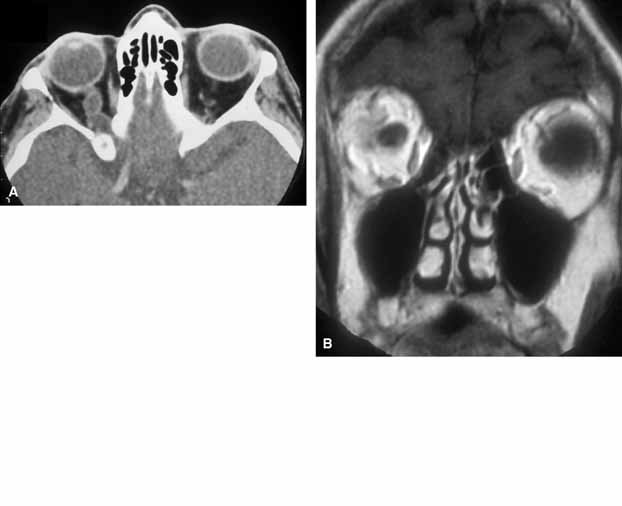

MRI is the radiographic imaging technique of choice, emphasizing high spatial resolution, fat-suppression techniques, and gadolinium contrast (Fig. 9).38 These techniques should assist in differentiating the patulous optic nerve sheath from optic nerve sheath meningioma in adults and from optic nerve glioma in children, which can be mimicked by cysts of the optic nerve sheath. Visual prognosis in these cases is guarded and the role of surgical treatment (optic nerve fenestration) is uncertain.

Fig. 9 Axial (A) computed tomography scans show enlarged right optic nerve sheath. The dilated optic nerve sheath is seen in a coronal plane (B) and is filled with cerebrospinal fluid in a T1-weighted magnetic resonance scan.